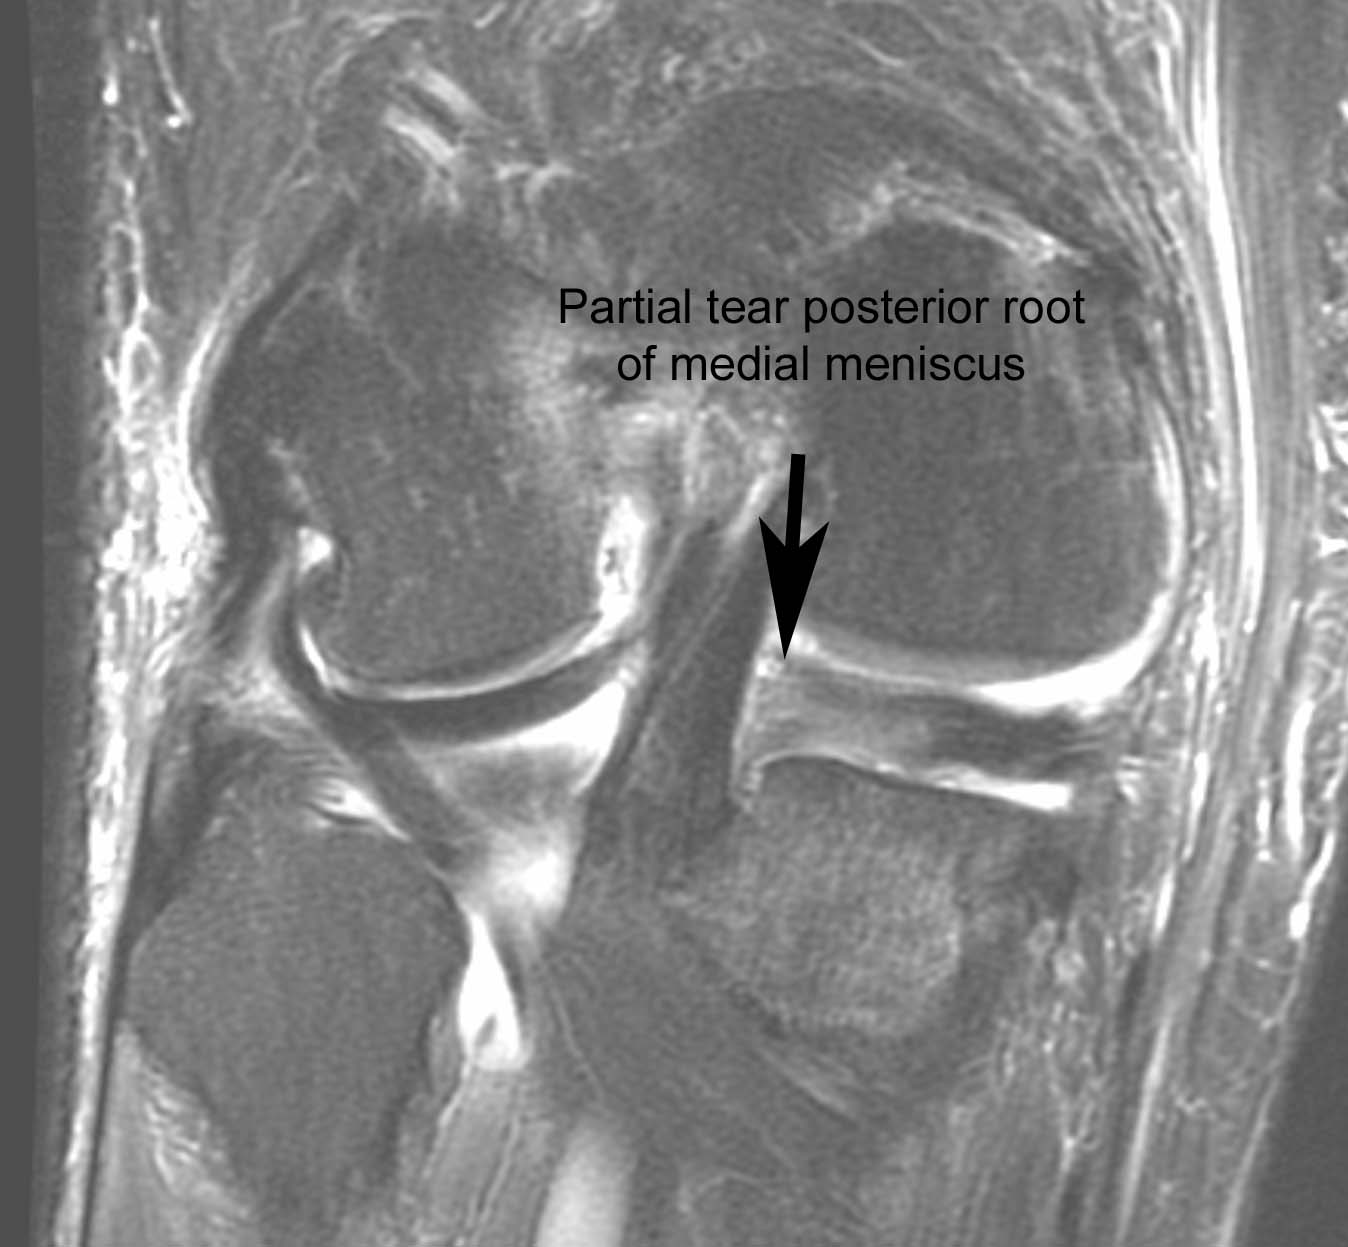

Figure 4 for case Disrupted ACL graft

Figure 4